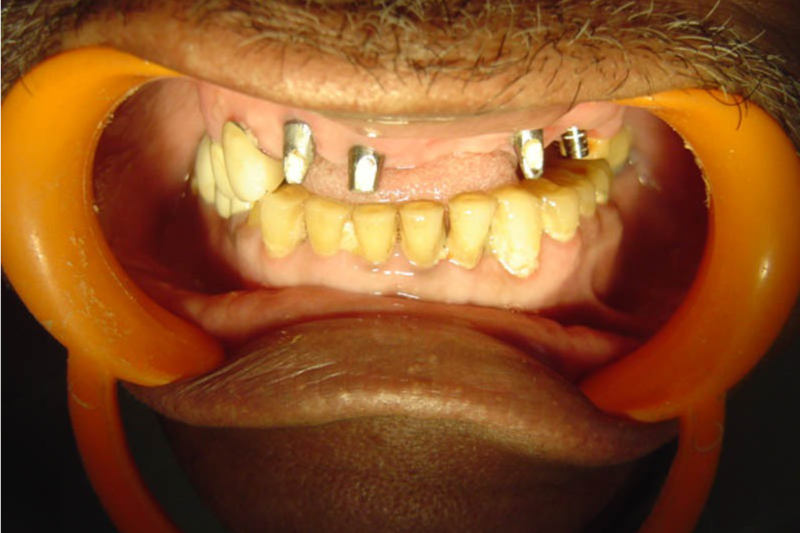

All on 4 All On 6 Implants

All on 4 or all on 6 treatment concepts is a graft less solution that provides patient with a fixed full arched prosthesis on the day of the surgery.

This treatment concept was developed to maximize the use of available remnant bone in atrophic jaws, allowing immediate function and avoiding regenerative procedures that increase the treatment costs and patient morbidity, as well as the complications inherent to these procedures

Advantage – graft less solution, immediate form and function, life changing, scientifically proven, very high success rate